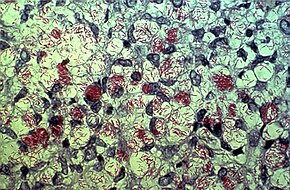

Leprosy is spread between people, although extensive contact is necessary.[3][9] About 95% of people who contract M. leprae do not develop the disease.[10] Spread is thought to occur through a cough or contact with fluid from the nose of a person infected by leprosy.[9][10] Genetic factors and immune function play a role in how easily a person catches the disease.[10][11] Leprosy does not spread during pregnancy to the unborn children, or through sexual contact.[9] Leprosy occurs more commonly among people living in poverty.[3] The two main types of disease – paucibacillary and multibacillary – differ in the number of bacteria present.[3] A person with paucibacillary disease has five or fewer poorly pigmented numb skin patches while a person with multibacillary disease has more than five skin patches.[3] The diagnosis is confirmed by finding acid-fast bacilli in a biopsy of the skin.[3]

Skin lesions can be single or many, and usually hypopigmented, although occasionally reddish or copper-colored.[63] The lesions may be flat (macules), raised (papules), or solid elevated areas (nodular).[63] Experiencing sensory loss at the skin lesion is a feature that can help determine if the lesion is caused by leprosy or if the lesion is caused by another disorder such as tinea versicolor.[63][64] Thickened nerves are associated with leprosy and can be accompanied by loss of sensation or muscle weakness, but without the characteristic skin lesion and sensory loss, muscle weakness is not considered a reliable sign of leprosy.[63]

In some cases, acid-fast leprosy bacilli in skin smears are considered diagnostic; however, the diagnosis is typically made without laboratory tests, based on symptoms.[63] If a person has a new leprosy diagnosis and already has a visible disability due to leprosy, the diagnosis is considered late.[33]